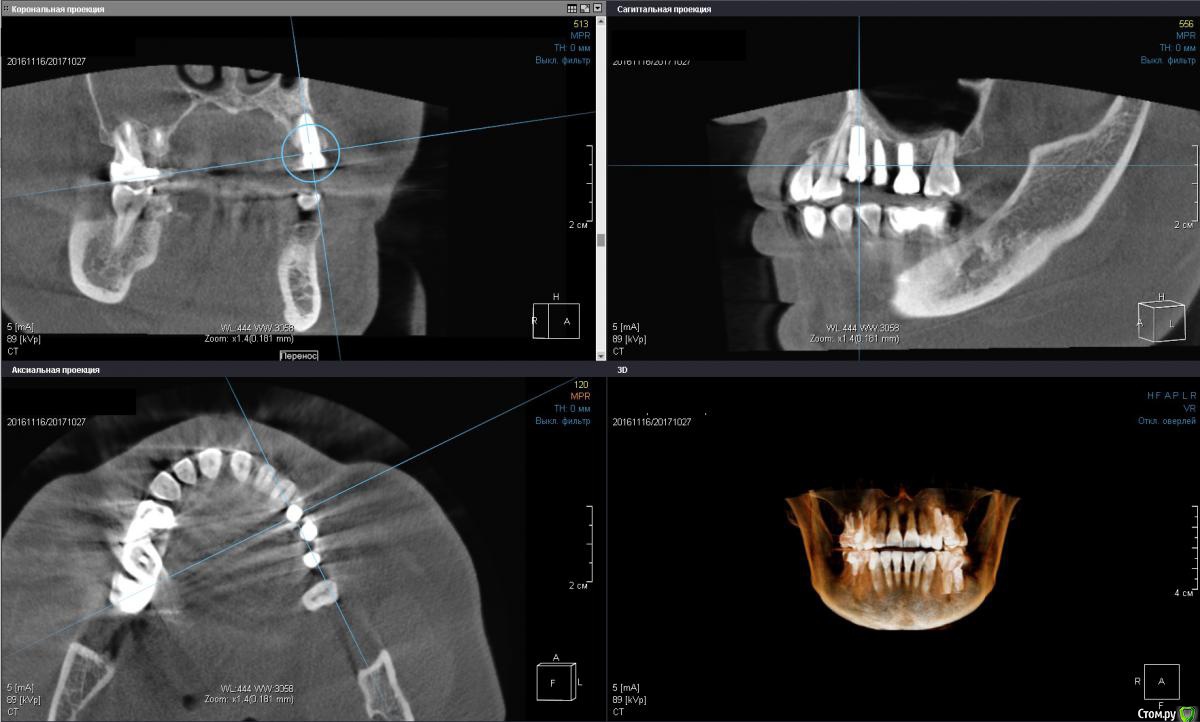

Irouil Опубликовано 2 ноября, 2017 Поделиться Опубликовано 2 ноября, 2017 Коллеги, очень прошу подсказки. Буду очень признателен за помощь. Вопрос пл 2.4 (первый товарищ из 3). Клиника такова: одномоментно с удалением был установлен винт, все проходило без эксцессов, через 4 месяца закрутил формики на 25 Нсм, при выкручивании 2.4 вышел вместе с фдм (моя глупость, имхо). Оставил на месяц, через месяц пилотным сверлом посерединке прошелся и поставил такой-же винт обратно, торк нормальный (точно не помню), все хорошо заживало. Где-то через месяц после установки случился казус - вестибулярно от фдм видимо что-то под манжету попало, пациенка затянула что-то с визитом, когда пришла сделал разрез по переходой, получил гной, перкуссия имплантата во всех направлениях чистая. Сегодня 5,5 месяцев с переустановки, имплантат звенит при перкуссии, снаружи все выглядит прекрасно (пальпация везде чистая, манжеты выглядят гладко, розово) НО! При выкручивании формика с пальчикового торка пациентка реагирует (говорит, что больно, но может просто чувствует - тут такие страхи перед всем, даже при анестезиях всегда слезы и квазиистерики). Притом, я уже не выдержал и под анестезией дал торк 15 на фдм туда и обратно - все чисто. Кт обе актуальные, вторая с толщиной среза 2 мм примерно. Че делать то? Планируется общая конструкция 2.4, 2.5, 2.6 Ссылка на комментарий

Irouil Опубликовано 2 ноября, 2017 Автор Поделиться Опубликовано 2 ноября, 2017 Ах, да, тройка тоже при перкуссиях/обдувах чистая как слеза младенца Ссылка на комментарий